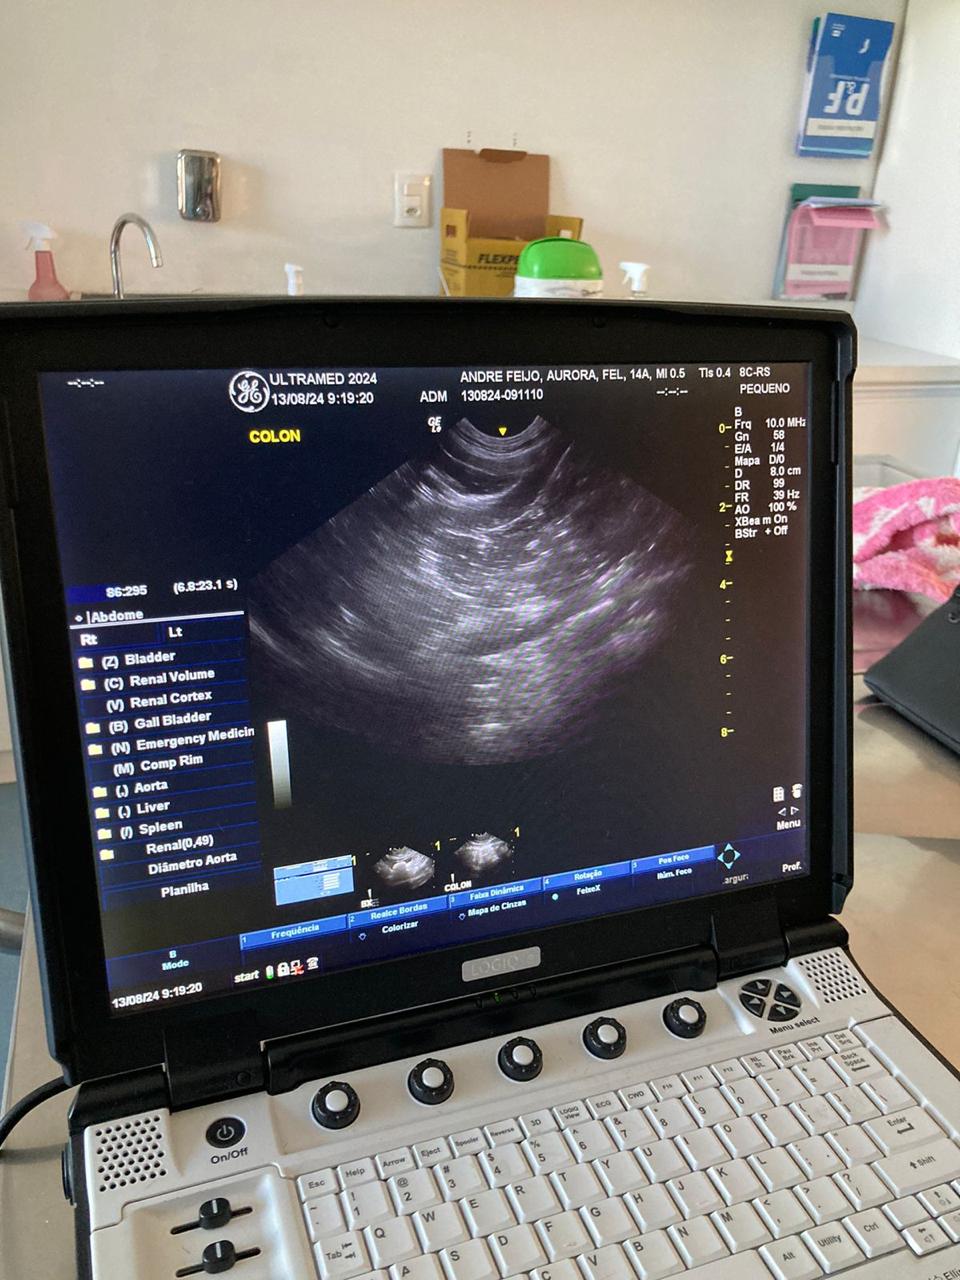

O ultrassom cachorro em novo hamburgo é um exame complementar não invasivo, que utiliza ondas sonoras para criar imagens detalhadas dos órgãos internos dos animais, auxiliando no diagnóstico de diferentes patologias.

Através de um transdutor que emite ondas sonoras de alta frequência, o veterinário consegue visualizar em tempo real as estruturas internas do animal, como fígado, rins, baço, intestinos e órgãos reprodutivos.